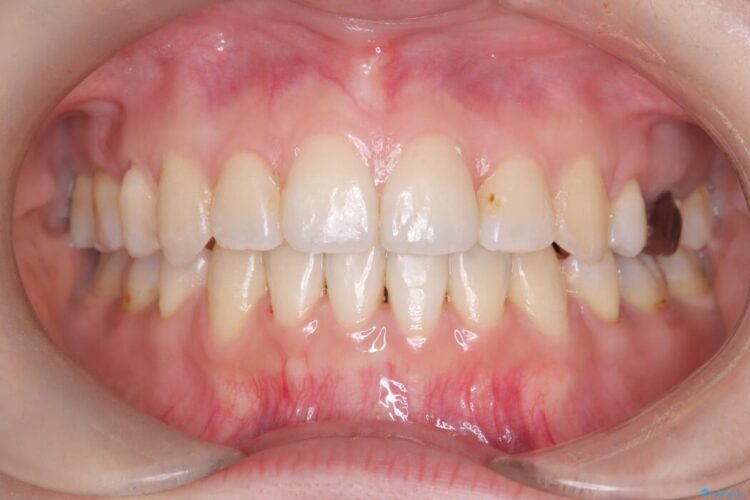

口元の突出感が改善され、大変ご満足いただけました。